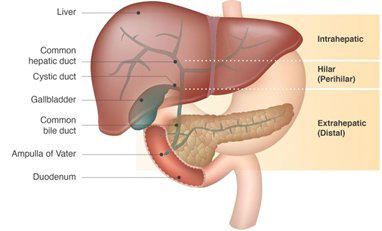

Galwegkanker (ook wel cholangiocarcinoom of CCA, genoemd) is kanker van de galwegen.

De galwegen zitten in de bovenbuik en lopen voor een deel door de lever. Door de galwegen stroomt gal van de lever naar de darmen. Gal is een belangrijk voor het verteren van het eten. Vooral voor opname van voedingstoffen zoals vetten en vitamines.

Afhankelijk in welk deel van deze galwegen de galwegkanker zich ontwikkeld, wordt het opgedeeld in 3 types en 2 hoofdgroepen:

- Intrahepatisch (liggend in de lever)

Intrahepatisch (perifeer) galwegkanker (cholangiocarcinoom, iCCA).

Ontstaat in de (kleinere) galwegen die in de lever liggen. - Extrahepatisch (liggend buiten de lever)

- Hilair of Perihilair galwegkanker (cholangiocarcinoom, pCCA of ook wel Klatskin tumor):

- Ontstaat net buiten de lever, daar waar de linker en rechter galwegtakken van de lever bij elkaar komen.

- Distaal galwegkanker (cholangiocarcinoom):

- Ontstaat ergens in de hoofdgalweg welke loopt van de lever naar de 12-vingerige darm (duodenum).

Andere vormen van kanker van het galwegsysteem zijn galblaaskanker en Papil van Vater kanker. Hier gaat deze folder niet verder op in.

Figuur 1: Cholangiocarcinoom kan elk deel van het galwegsysteem aantasten.

Illustratie: AMMF 2022©